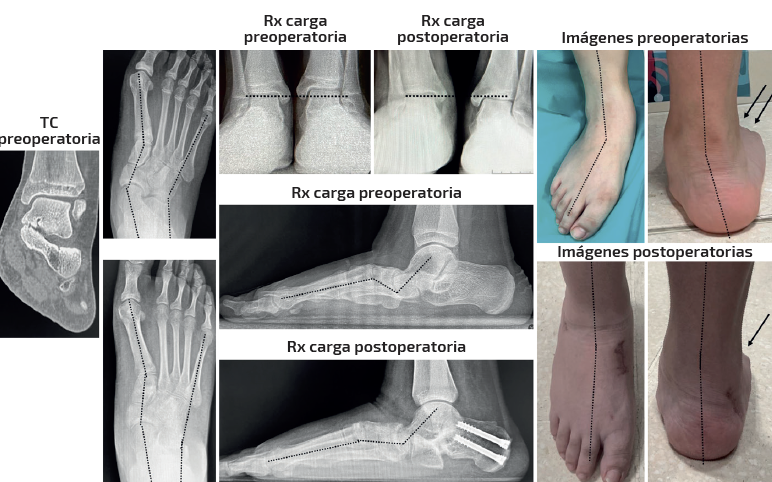

Caso 1 (Figura 4)

Se trata de una paciente mujer de 25 años afecta de dolor medial y sinus tarsi. Antecedente en adolescencia de esguinces laterales frecuentes. Diagnosticada previamente de forma errónea de microinestabilidad de tobillo. Evidencia de coalición ósea talocalcánea en pruebas de imagen y deformidad clínica y radiológica con predominio de abducto. Subtalar rígida. Tipo IIB de Myerson. Tratamiento: osteotomía de alargamiento de la columna externa con cuña de metal trabecular como único gesto quirúrgico. Seguimiento: 2 años. Capaz de caminar largas distancias sin dolor. Mejoría de la alineación clínica y en las radiografías dorsoplantar y de Saltzman. Sin cambios en las ángulos sagitales.